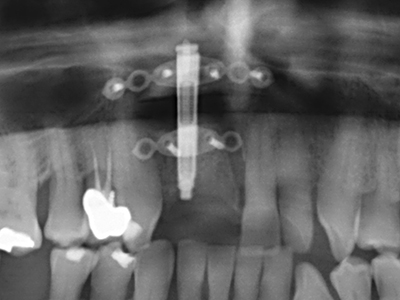

Si es preciso realizar intervenciones quirúrgicas en las que el hueso está en contacto directo con estructuras sensibles, como son los vasos sanguíneos o los nervios, los instrumentos rotativos presentan un enorme potencial de provocar lesiones iatrogénicas. Así, precisamente en la representación de nervios después de una lesión iatrogénica, o en el transcurso de la lateralización de un nervio para resecciones, reconstrucciones o incorporación de implantes, los equipos piezoeléctricos pueden resultar muy útiles para preparar la tapa ósea y retirar las partes de tejido duro cercanas al nervio (fig. 17-20). Por lo general, un ligero contacto del cordón nervioso con el inserto piezoeléctrico no tiene consecuencia alguna; ahora bien, un procedimiento poco cuidadoso con movimientos tipo sierra o piezas de trabajo sobre la base ósea aún existente puede provocar lesiones nerviosas temporales o incluso permanentes. Con todo, el riesgo de sufrir una lesión de este tipo se considera significativamente inferior que en los casos en los que se utilizan sierras y fresas (Pereira, Gealh et al. 2014).